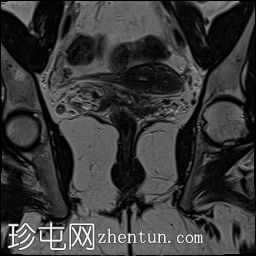

冠状位

STIR序列

子宫外底轮廓清晰,肌层较厚,将子宫内膜腔分隔成两个腔,纤维层较薄,向下延伸至宫颈外口。子宫内膜厚度正常,两个子宫腔交界区清晰,未见明显的实性局灶性病变。

本病例展示了典型的纵隔子宫影像学表现:增厚的肌层隔膜将子宫内膜腔分隔成两个腔,并有一层薄的纤维隔膜延伸至子宫颈外口水平,符合完全纵隔子宫的特征。

在MRI图像上,纵隔子宫通常大小正常,但每个子宫腔的形态均小于正常子宫腔。

隔膜可能由纤维组织(T2信号低)、肌层组织(中等信号)或两者共同构成,如本病例所示。